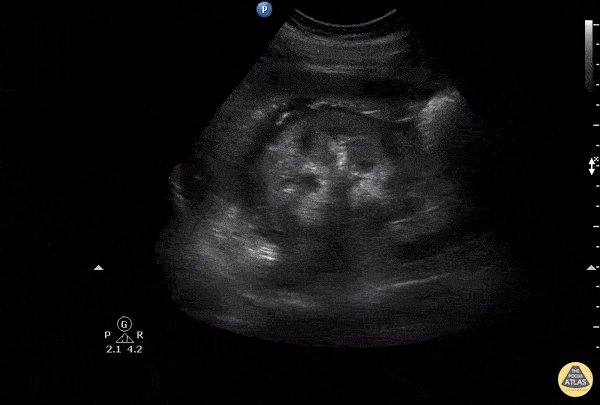

Renal/GU - Calyceal Rupture

add desp Image courtesy of Robert Jones DO, FACEP @RJonesSonoEM Director, Emergency Ultrasound; MetroHealth Medical Center; Professor, Case Western Reserve Medical School, Cleveland, OH View his original post here